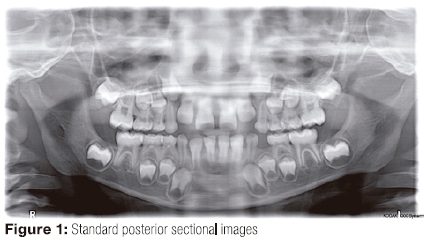

Focal trough layer the area between the x ray source and the image receptor that will be imaged distinctly on the panoramic radiograph.

Ala tragus line panoramic. Ikfanson hing university of alabama scho. An imaginary plane or line from the orbital ridge to the acoustic. An imaginary plane or line from the ala of the nose. The roots of the anterior teeth are in the image and the posterior teeth are the same size on each.

The angle between this line and the horizontal plane is 3on the panorex and 4on the. Focal trough layer that area between the x ray source and the image receptor that will be imaged distinctly on the panoramic. In other words the ala of the nose should be slightly inferior to the height of the tragus. These zones are as follows.